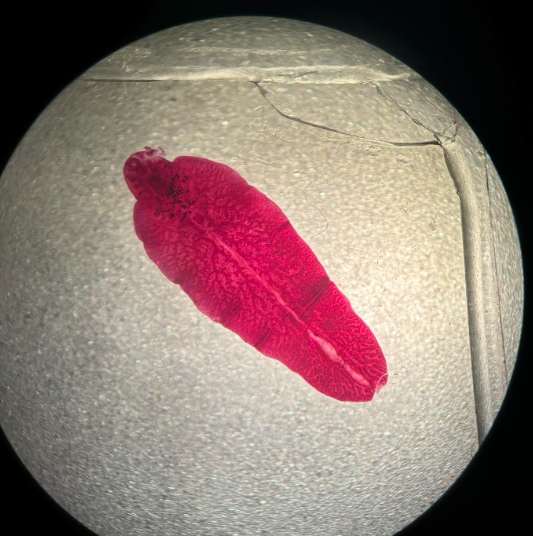

fasciolopsis buski postać dojrzała